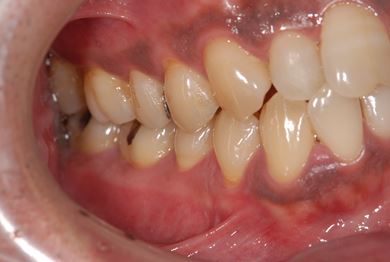

セラミック治療+歯肉歯槽骨整形術

| 性別/年齢 | 男性 / 45歳 | ||||||||||||||||||||||||||||||||

| 主訴 | 詰め物をしている歯が割れてしまったので、治療して欲しい。 | ||||||||||||||||||||||||||||||||

| 治療方針 | セラミック治療にて、審美的回復を行う。 | ||||||||||||||||||||||||||||||||

| 治療内容 | メタルボンドセラミッククラウン1本(メタルボンドセラミック用土台1本)、歯肉歯槽骨整形手術 | ||||||||||||||||||||||||||||||||

| 総治療費 | 157,185円 | ||||||||||||||||||||||||||||||||

| 治療期間 | 7ヶ月 |